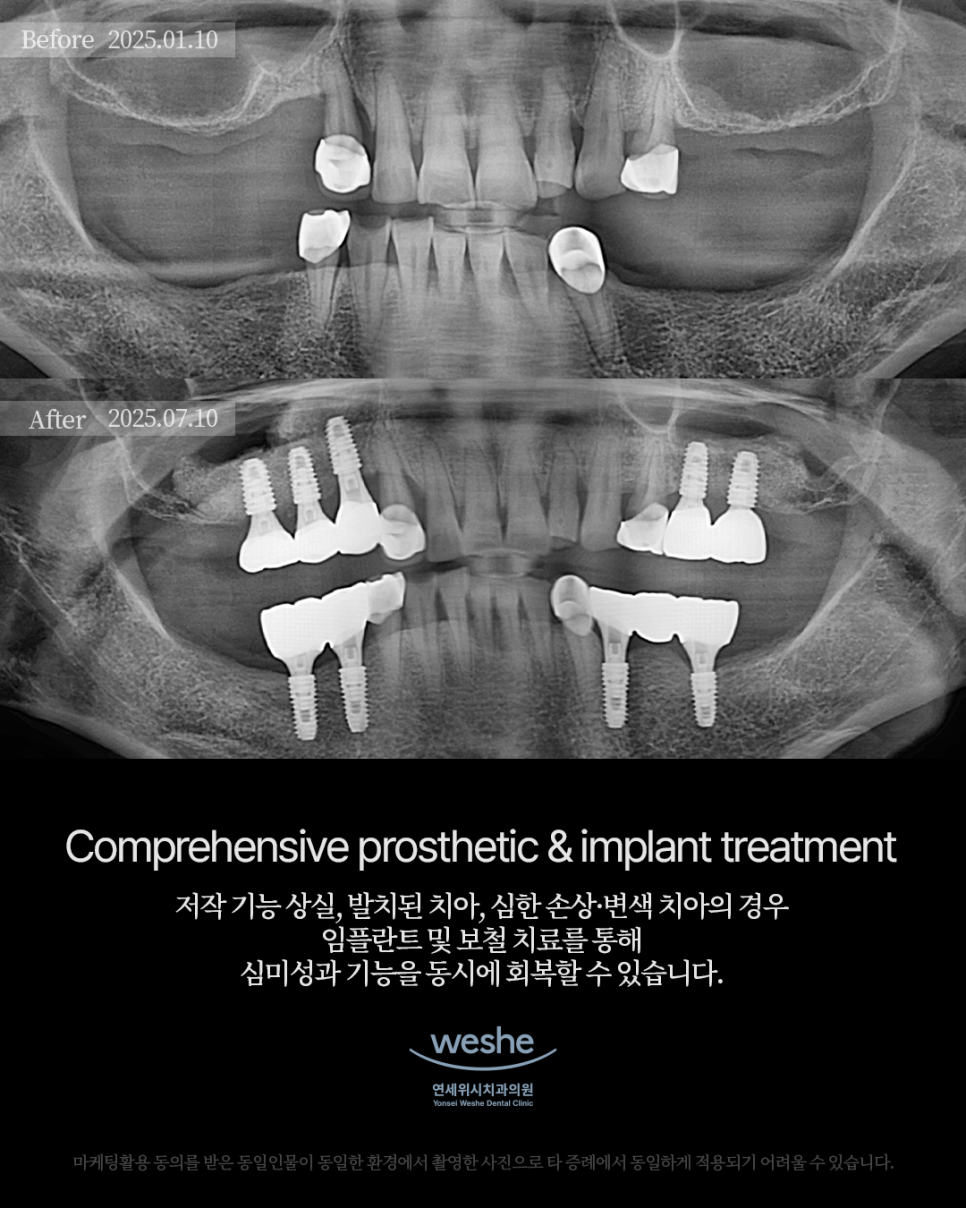

This was a case in which implant placement was difficult because there was insufficient available bone in the molar area.

Based on an accurate CT diagnosis,

a sinus lift procedure and bone grafting were performed together

to improve the jawbone environment

so that stable fixture placement would be possible.

Using a navigation guide,

the implant was placed at the optimal position and angle,

resulting in a safer and more predictable outcome.

After sufficient healing,

a natural-looking molar crown was fabricated

with consideration for the individual’s bite and tooth shape,

restoring both function and aesthetics.

Take a look at the completed transformation in a short period of time

through the Before & After images.